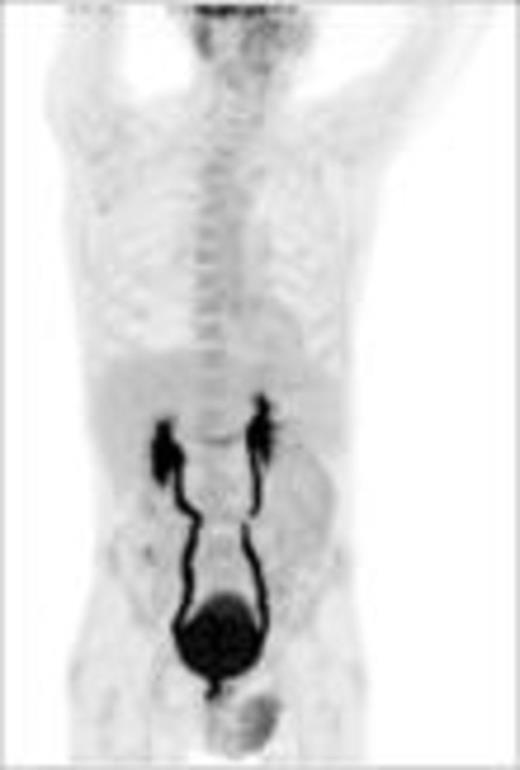

Baseline (pt#1) after 1 x PREBEN (pt#1)